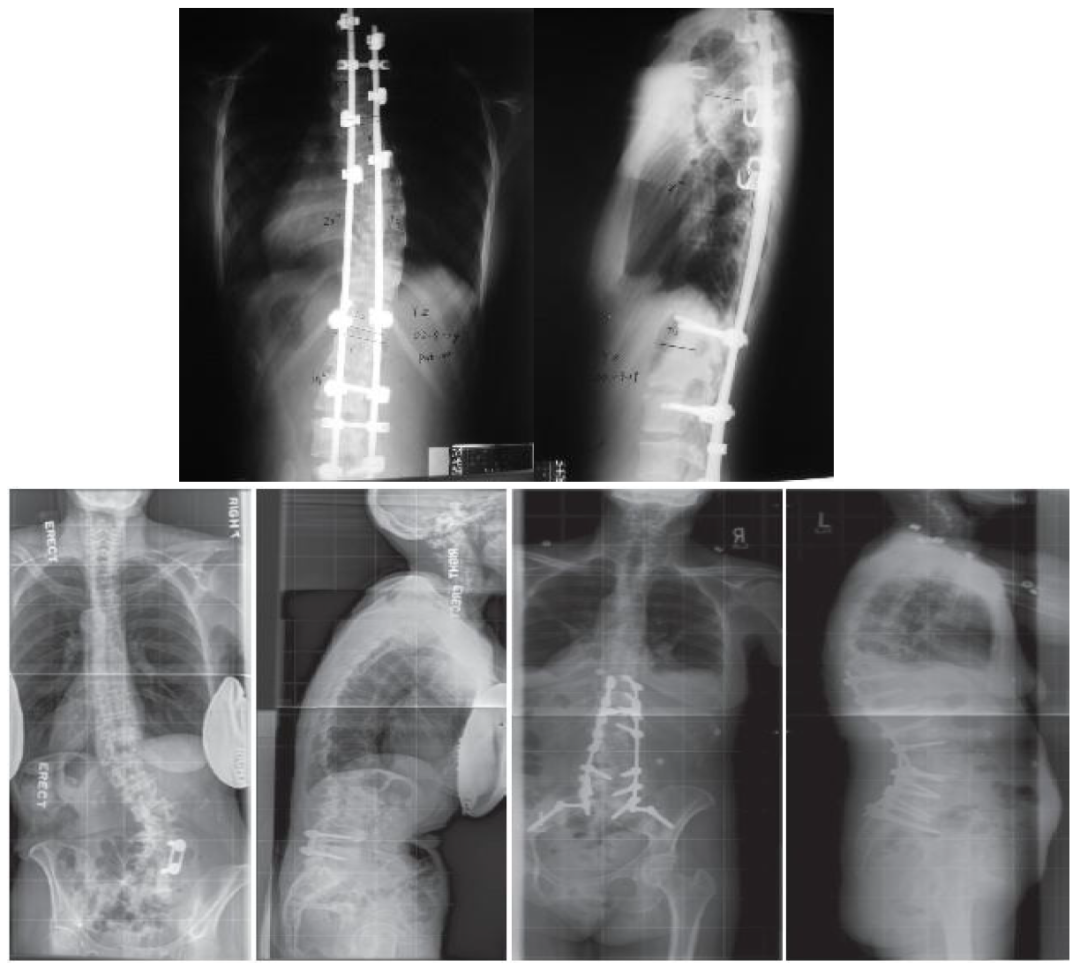

神經(jīng)肌肉型脊柱側(cè)凸

手術(shù)的固定通常要從上胸椎(T1或者T2)融合到骨盆

脊柱矯形術(shù)后效果